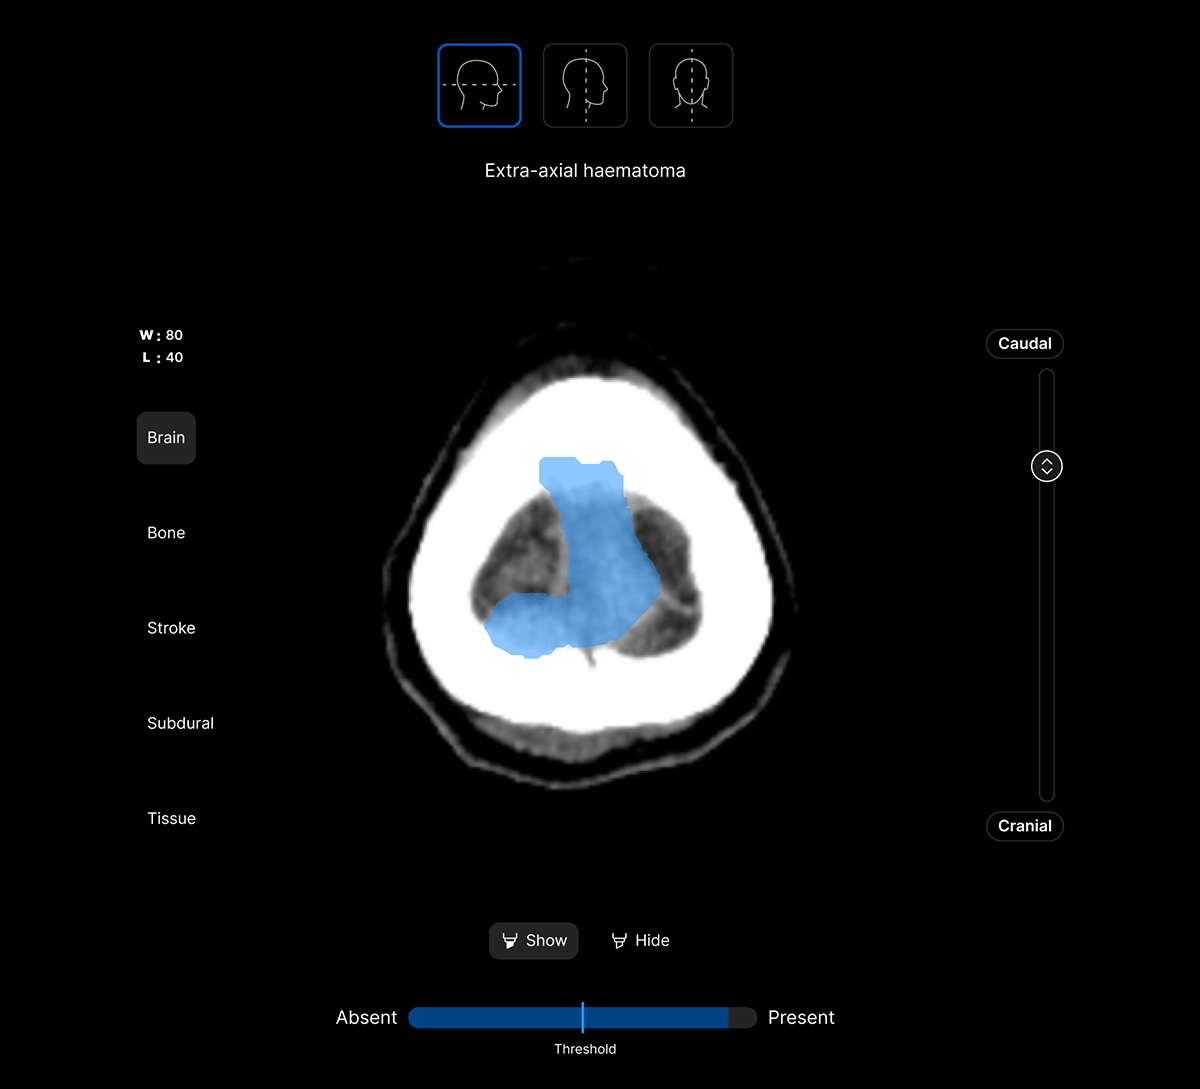

The UI integrates seamlessly with PACS/ RIS, displaying a resizable, no-click overlay window with findings and localisation.

Customisable features.

Customisable thresholds, for individual findings (to optimise for sensitivity / specificity) to tailor the workflow to your clinical setting or population.